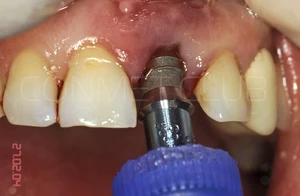

Через 3 месяца временная коронка удалена и начато изготовление стандартной металлокерамической коронки. Вид на имплантат КОНМЕТ сразу после удаления временной коронки.

Из-за глубокого резцового перекрытия пришлось сильно утачивать стандартный, прямой абатмент. Безусловно не самая простая ортопедическая ситуация с сложно прогнозируемым сроком службы.